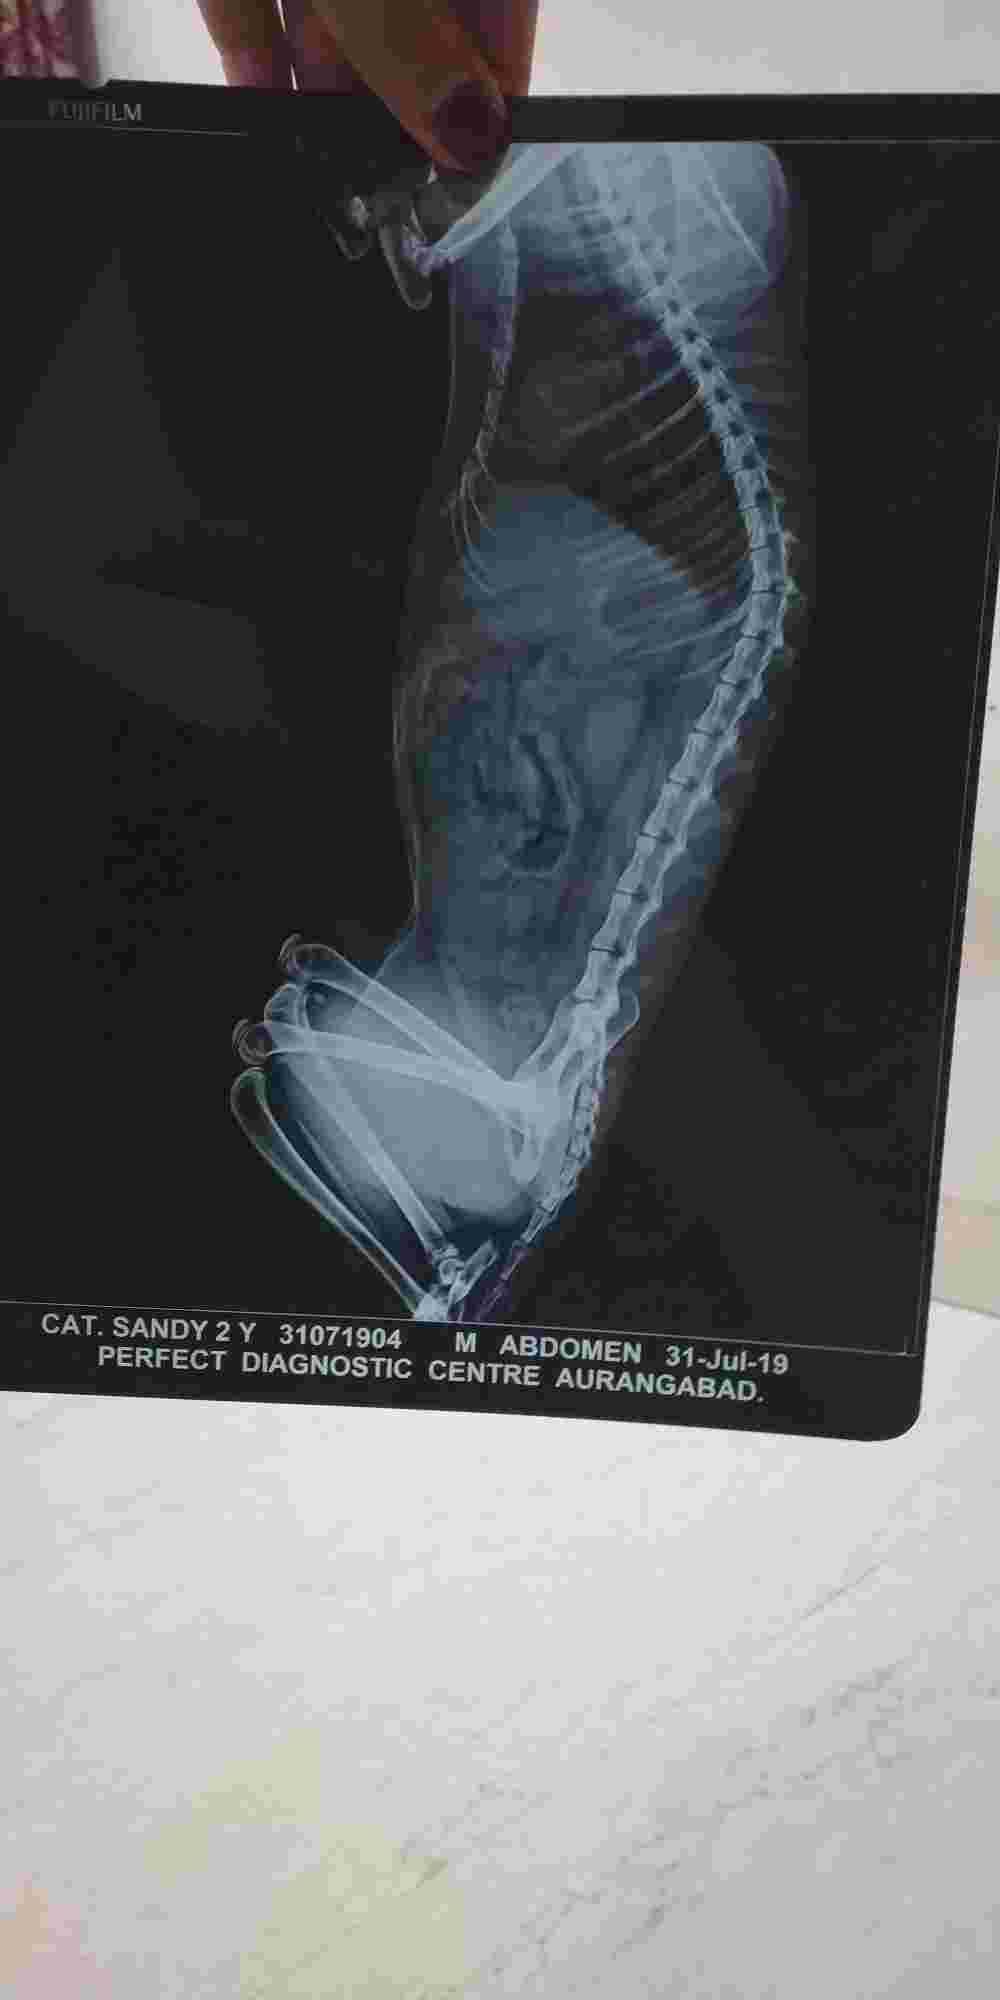

Sandy he is not having urine properly he is doing few drops of urine again an again 5-10ml per time and also having vomiting again again we have taken an x-ray of sandy he is two years old recently he lost his partner female angel . So plz help me what to do .vet has has told i think that he is having stone He is not sure about this when he saw the x-ray he told that sandy is not having stone then he proscribed me an tablet and told that he us having stone. Plz check the x-ray n help me

I'm so sorry but the x-rays are too grainy and blurry when we try to enlarge them. We cannot tell anything from these. Can you please post again with clearer photos? Also, the positioning of your cat in the x-rays is not good. The back legs need to pulled completely backwards so we can see the entire urethra. I agree with your vet and just based on the clinical signs I would say a urethra partial obstruction is likely (crystals or a stone). I would suggest the following: 1. Blood testing to check kidney function 2. Urine test to look for crystals, infection, etc. 3. Sandy should be sedated and a urethral catheter passed. Often times if there are crystals and/or a small stone blocking the urethra they can be flushed backwards into the bladder. Then a special diet can be prescribed to help dissolve the crystals/stones.